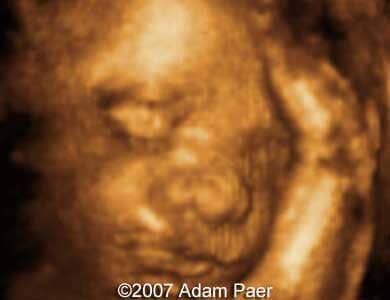

Dacryocystocele, unilateral Adam Paer, MD. Article Published: Jun 26, 2007 Costa Rica Case report These are some third trimester ultrasound images showing unilateral dacryocystocele..Images 1 and 2: Transverse scans at the level of the fetal eyes showing unilateral dacryocystocele. Images 3 and 4: Parasagittal scans showing dacryocystocele next to the eyeball. Image 5: 3D image showing small prominences of the medial canthus representing dacryocystocele. Discussion Board Start a discussion about this article Add to Favorites Favorite